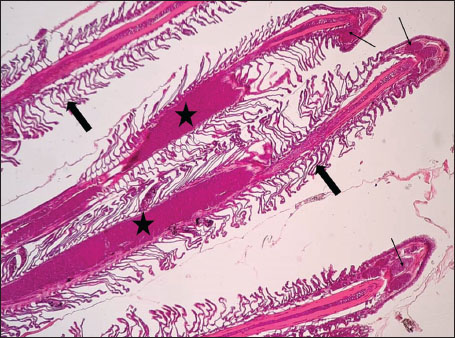

ABSTRACTBackground: The Mediterranean Sea has undergone significant ecological changes in recent decades, partly due to the introduction of non-native species. Lagocephalus sceleratus is an invasive Lessepsian species widely distributed in the Mediterranean, increasingly abundant along the Libyan coast, and potentially exposed to chronic environmental stressors. This species represents an important model for baseline pathological assessment in newly colonized marine environments. Aim: This study provides a descriptive histopathological assessment of kidney and gill tissues in adult L. sceleratus to document baseline tissue alterations without inferring direct environmental or pollution-related causation. Methods: A total of 150 adult specimens were collected from four Libyan coastal locations. Tissues were processed using standard histological techniques and evaluated semi-quantitatively (+, ++, +++) for lesion severity. Lesion severity grades were converted into ordinal numerical data and summarized using descriptive statistical approaches only. Results: Kidney tissues exhibited tubular degeneration, Bowman’s capsule dilatation, vascular congestion, extensive melanomacrophage centers (MMCs), and inflammatory lesions. Gill tissues showed disorganization of secondary lamellae, epithelial hyperplasia, edema, aneurysmal dilatations, vascular congestion, and MMC proliferation, some of which were associated with histologically observed parasitic structures. Conclusion: The observed alterations represent descriptive baseline tissue changes and should not be interpreted as direct evidence of pollution or specific environmental stressors. These findings provide reference data for future comparative pathological and ecological studies. Keywords: Lagocephalus sceleratus, Kidney, Gills, Histopathology, Melanomacrophage centers, Invasive species, Mediterranean Sea. IntroductionIn recent decades, the Mediterranean Sea has undergone profound ecological changes driven by the arrival and establishment of non-native marine species. Among these, Lagocephalus sceleratus has emerged as one of the most impactful Lessepsian migrants, due to its rapid geographic expansion, high ecological adaptability, and the presence of the potent neurotoxin tetrodotoxin in its tissues. This species has been widely documented to alter local fish communities, affect fisheries, and pose public health risks, making it an important target for biological and environmental assessment across the region (Katikou et al., 2022; Christidis et al., 2024). Fish are widely recognized as sensitive biological organisms in aquatic ecosystems, particularly in coastal habitats that are exposed to anthropogenic pressures such as industrial effluents, agricultural runoff, and untreated wastewater (Pinna et al., 2023). Among fish organs, the gills and kidneys are commonly regarded as sensitive to environmental stress, as they respond to physiological and pathological changes under environmentally suboptimal conditions. The gills, due to their large surface area and continuous exposure to surrounding water, are often the first tissues to exhibit structural alterations when fish encounter pollutants (Shahid et al., 2022). Histopathological changes in gills observed in polluted environments include epithelial lifting, lamellar fusion, hyperplasia, increased mucous cell density, and focal necrosis, which collectively reflect early physiological stress and potential compromise of respiratory function (Osman, 2010; Shahid et al., 2022). Similarly, the kidneys play crucial roles in osmoregulation, excretion of metabolic waste, and detoxification, making them highly vulnerable to chronic or systemic toxic effects (Wahidi et al., 2025). Documented renal lesions associated with chemical exposure include tubular deterioration, glomerular shrinkage, interstitial edema, and infiltration of inflammatory cells. These structural alterations often coincide with underlying biochemical disruptions, such as oxidative stress, impaired detoxification pathways, and activation of apoptotic mechanisms (Bernet et al., 1999; Authman, 2015). Despite the growing body of research on the ecological and toxicological implications of L. sceleratus, detailed histopathological assessments of this species remain scarce, especially in the southern Mediterranean basin, where environmental conditions and pollution profiles may differ from those in other regions. To date, detailed tissue-level studies of L. sceleratus from the southern Mediterranean are lacking, which limits the understanding of how this invasive species responds physiologically to local environmental stressors (Shakman et al., 2019; Ulman et al., 2021; Mohmmed et al., 2023). Accordingly, the present study aims to provide a comprehensive descriptive evaluation of histopathological changes in the kidneys and gills of L. sceleratus. The study is designed as a baseline histopathological assessment, focusing on tissue-level alterations without establishing causal links to environmental pollution or physicochemical stressors. By documenting structural aberrations and pathological features, this study contributes reference data for future monitoring and comparative studies in Mediterranean coastal ecosystems. Materials and MethodsSample designA total of 150 adult specimens of L. sceleratus, including both sexes, were collected from four Libyan coastal locations: Talamitha (n=39), Susah (n=34), Ain El-Ghazala (n=30), and Khalij Al-Bambah (n=47). Fish ranged in total length from 51 to 66 cm and in weight from 1.5 to 3.5 kg. Only apparently healthy adults were included, while juveniles were excluded to avoid age-related histopathological variation. Sampling was conducted opportunistically with assistance from local fishermen. All specimens were collected within a comparable seasonal window to minimize seasonal histopathological variability. Sex was recorded when possible; however, sex-based histopathological comparisons were not performed, as this was beyond the descriptive scope of the study. Fish were transported on ice at +4°C and examined in the Pathology Laboratory, Faculty of Veterinary Medicine, Omar Al-Mukhtar University (Mohmmed et al., 2023). Specimens were collected from a range of depths (0.5–70 m), with the majority from shallow waters (<10 m) and a subset (approximately 50 fish) from deeper locations (>30 m). Environmental physicochemical parameters such as temperature, salinity, and dissolved oxygen were not measured; therefore, no direct associations between histopathological findings and environmental variables were assessed. Tissue processing and histopathological examinationTissue specimens were fixed in 10% neutral buffered formalin for 24 hours. Following fixation, the samples were transferred to 70% ethanol for storage at room temperature. Subsequently, the tissues were processed for routine histopathological examination following standard procedures (Paul and Chanda, 2017). Paraffin embedding was performed, and 5 µm-thick sections were prepared using a microtome. Sections were stained with hematoxylin and eosin (H&E) and examined under a light microscope. Photomicrographs of representative lesions were captured using a high-resolution digital camera. Histopathological alterations were evaluated using a semi-quantitative scoring system adapted from Hose et al. (1996), Moshaie-Nezhad et al. (2021), and Alshailabi et al. (2023), where lesion severity was graded as mild (+), moderate (++), or severe (+++). Lesion severity grades (+, ++, +++) were converted into ordinal numerical values (1–3) for descriptive summarization of lesion severity. Due to the descriptive baseline nature of the study and the absence of a reference control group, inferential statistical comparisons were not emphasized or applied. Lesion severity scores were therefore summarized descriptively to avoid overinterpretation of the findings. Scoring was performed independently by two experienced observers, and representative lesions were confirmed across three sections per organ to ensure consistency. Tissues with visible parasitic structures were described separately from non-parasitized tissues to avoid conflating parasite-associated lesions with non-specific tissue alterations. The functional implications of the observed lesions were interpreted in accordance with Flores-Lopes and Thomaz (2011). Ethical approvalAll animal experiments conducted in this study were approved by the Ministry of Higher Education & Scientific Research and the Libyan National Committee for Biosafety & Bioethics, Libya. All procedures were performed in accordance with the relevant ethical guidelines, with session number 21/CH/25, dated 26/05/2021. ResultsHistopathological examination of the kidneyHistopathological examination of the kidney tissues of L. sceleratus revealed multiple alterations. Prominent melanomacrophage centers (MMCs), necrotic areas, dilatation of Bowman’s capsules, and vacuolar degeneration were observed (Fig. 1), associated with interstitial lymphohematopoietic tissue (Fig. 2). Dilated and congested blood vessels and extensive MMCs were also noted (Fig. 3). Renal degeneration surrounding lymphohematopoietic tissue, large clusters of MMCs, and thickened, congested vessel walls within fibrotic areas were evident (Fig. 4). Atrophic renal degeneration with necrotic and vacuolar changes was observed (Fig. 5). Severe inflammatory infiltration of lymphatic cells and granulomas with necrotic centers, surrounded by fibrous tissue, was detected (Figs. 6–7).

Fig. 7. Histopathology of the kidney in an adult L. sceleratus showed the atrophic renal degeneration (stars), dilatation of Bowman’s capsules (thick arrows), and a granuloma (head arrow). ×400 H&E. Histopathological examination of the gillsThe gill sections of adult L. sceleratus exhibited multiple structural alterations. Secondary lamellae showed marked disorganization, while gill filaments displayed club-shaped deformities and occasional aneurysmal dilatations (Fig. 8). Vascular congestion with telangiectatic changes and proliferation of MMCs were also observed (Figs. 9–10). Edematous changes in primary lamellae, separation of the epithelial layer, lamellar aneurysms, and epithelial hyperplasia were documented (Figs. 10–11). Focal damage to secondary lamellae, disruption of lamellar architecture, presence of lamellar aneurysms, and unidentified parasitic structures were observed (Fig. 12). Pronounced vascular congestion and dilatation of lamellae due to red blood cell accumulation were noted (Fig. 13).

Fig. 12. Histopathology of the gills in an adult L. sceleratus showing the damage to secondary lamellae and lamellar disorganization (thick arrows), lamellar aneurysm (head arrows), and unidentified parasites (thin arrows). ×40 H&E.

Fig. 13. Histopathology of the gills in an adult L. sceleratus showing congestion and telangiectasia of gill filament vessels (thick arrows) and lamellar dilation due to RBC accumulation (head arrows). ×40 H&E. Gill lesions were described separately for tissues with visible parasites and those without parasitic structures to improve interpretative clarity. Summary of lesionsHistopathological alterations in both kidney and gill tissues were classified using a semi-quantitative scoring system (+, ++, +++) (Fig. 14).

DiscussionThe present study revealed pronounced histopathological alterations in both the kidneys and gills of L. sceleratus collected along the Libyan coast. Kidney lesions, including tubular degeneration, Bowman’s capsule dilatation, proliferation of MMCs, vascular congestion, and inflammatory infiltration, were associated with histologically detected structures, but no parasitic structures were detected in kidney tissues. These patterns are commonly reported in marine teleosts exposed to chronic environmental stressors (Ali et al., 2014; Steinel and Bolnick, 2017; Carreras-Colom et al., 2022). These lesions should be interpreted as descriptive indicators of physiological stress rather than direct evidence of chemical pollution or causality, consistent with Flores-Lopes and Thomaz (2011). Vascular abnormalities, including congestion and thickened vessel walls, were evident, which may reflect chronic circulatory disturbances or inflammatory responses rather than acute toxicity (Bernet et al., 1999; Thophon et al., 2003). Interstitial lymphohematopoietic tissue, inflammatory cell infiltration, and granulomatous formations suggest that parasitic or microbial challenges could contribute to renal lesions. Despite these histopathological changes, the sampled fish appeared healthy at capture, demonstrating the potential physiological resilience of marine teleosts. Fish kidneys possess compensatory mechanisms, and gills serve critical osmoregulatory and excretory functions, allowing survival despite structural alterations (Evans et al., 2005; Hwang et al., 2011; Hinton et al., 2018; Leone et al., 2018). Gradual development of renal lesions likely enables adaptation without acute organ failure. Gill tissues also exhibited pronounced alterations, including disorganization of secondary lamellae, club-shaped filament deformities, lamellar aneurysms, epithelial hyperplasia, and edema. These changes are consistent with chronic, sublethal tissue responses observed descriptively, without inferring specific environmental stressors or chemical toxicity (Sinha et al., 2014; Carvalho et al., 2020; Pramanik and Biswas, 2024). Unidentified parasitic structures, morphologically consistent with metazoan parasites, were observed based on histological appearance. Lesions were described separately for tissues with visible parasites and non-parasitized tissues to improve interpretative clarity (Sitjà-Bobadilla, 2008; Biller and Chagas, 2022). The proliferation of MMCs in gills reflects an immune response to tissue damage and cellular debris, reinforcing the descriptive nature of the findings. Vascular congestion and lamellar dilation due to RBC accumulation may indicate sublethal circulatory stress, but these observations are descriptive and not confirmed by physiological measurements (Triebskorn et al., 2007; Hasan et al., 2022). Moderate lesions (++), as summarized in Table 1 and illustrated in Fig. 14, were predominant, reflecting chronic, sublethal tissue responses rather than lethal injury. Overall, the kidney and gill lesions detected in L. sceleratus reflect chronic, sublethal tissue responses observed descriptively. No causal relationships with environmental stressors or chemical pollution can be inferred. Future studies incorporating water and sediment analyses, parasitological identification, and reference/control populations are recommended to strengthen the interpretation of these histopathological responses as potential biomarkers. LimitationsThis study is limited by the absence of environmental physicochemical data, the lack of a reference or control site, and the descriptive nature of the histopathological assessment. In addition, parasitic structures were not identified to species level, and quantitative prevalence metrics were not calculated. Accordingly, the findings should be interpreted as baseline descriptive observations rather than indicators of specific environmental stressors or pollution sources. ConclusionHistopathological examination of the kidneys and gills of L. sceleratus revealed tissue-level changes that serve as descriptive baseline data. Moderate to severe alterations were observed, including tubular degeneration, MMC proliferation, vascular congestion, secondary lamellae disorganization, and epithelial hyperplasia. No parasitic structures were detected in kidney tissues, while parasitic structures were observed only in some gill tissues and described separately. Despite these alterations, the species exhibits physiological compensation mechanisms, including renal adaptive responses and gill-mediated osmoregulation, supporting resilience under sublethal stress conditions. These findings are descriptive and should not be interpreted as direct evidence of environmental contamination or causation. All observations represent baseline histopathological data, intended to support future comparative and environmentally integrated studies rather than establish causal relationships. AcknowledgmentsThe authors sincerely thank the staff of the Pathology and Clinical Pathology Department (Faculty of Veterinary Medicine, Omar Al-Mukhtar University) and the Zoology Department (Faculty of Science, Omar Al-Mukhtar University) for their valuable support. Conflict of interestThe authors declare that there is no conflict of interest. FundingThis research received no specific grant. Authors' contributionsEda M. A. Alshailabi and Sana A. A. Mohammed contributed to the project idea and design, and Sana A. A. Mohammed and Ismail M. Hdud executed the study. Eda M. A. Alshailabi drafted and wrote the manuscript. Sana A. A. Mohammed and Samia M. Efkeren reviewed the manuscript critically. All authors have read and approved the final manuscript. Data availabilityAll data supporting the findings of this study are available within the manuscript. ReferencesAli, A.O., Hohn, C., Allen, P.J., Ford, L., Dail, M.B., Pruett, S. and Petrie-Hanson, L. 2014. The effects of oil exposure on peripheral blood leukocytes and splenic melano-macrophage centers of Gulf of Mexico fishes. Mar. Pollut. Bull. 79(1–2), 87–93; doi:10.1016/j.marpolbul.2013.12.036 Alshailabi, E., I.Al-Zail, N. and Abraheem, R. 2023. The effects of cigarette smoke on the epididymal tissues in adult male albino rats and the ameliorative effect of the Sidr honey. Libyan. J. Med. Res. 16(2 B), 79–92; doi:10.54361/LJMR.16.2B.08 Authman, M.M. 2015. Use of fish as bio-indicator of the effects of heavy metals pollution. J. Aquac. Res. Develop. 6, 328; doi:10.4172/2155-9546.1000328 Bernet, D., Schmidt, H., Meier, W., Burkhardt‐Holm, P. and Wahli, T. 1999. Histopathology in fish: proposal for a protocol to assess aquatic pollution. J. Fish Dis. 22(1), 25–34; doi:10.1046/j.1365-2761.1999.00134.x Biller, J.D. and Chagas, E.C. 2022. Mechanisms of resistance and tolerance against parasites in fish: the impairments caused by Neoechinorhynchus buttnerae in Colossoma macropomum. Anais. Da. Academia. Brasileira. De. Ciências. 94(4), e20210258; doi:10.1590/0001-3765202220210258 Carreras-Colom, E., Constenla, M., Dallarés, S. and Carrassón, M. 2022. Natural variability and potential use of melanomacrophage centres as indicators of pollution in fish species from the NW Mediterranean Sea. Mar. Pollut. Bull. 176, 113441; doi:10.1016/j.marpolbul.2022.113441 Carvalho, T.L.A.D.B., Do Nascimento, A.A., Gonçalves, C.F.D.S., Dos Santos, M.A.J. and Sales, A. 2020. Assessing the histological changes in fish gills as environmental bioindicators in Paraty and Sepetiba bays in Rio de Janeiro, Brazil. Latin. Am. J. Aquatic. Res. 48(4), 590–601. Christidis, G., Batziakas, S., Peristeraki, P., Tzanatos, E., Somarakis, S. and Tserpes, G. 2024. Another one bites the net: assessing the economic impacts of Lagocephalus sceleratus on small-scale fisheries in Greece. Fishes 9(3), 104; doi:10.3390/fishes9030104 Evans, D.H., Piermarini, P.M. and Choe, K.P. 2005. The multifunctional fish gill: dominant site of gas exchange, osmoregulation, acid-base regulation, and excretion of nitrogenous waste. Physiological Rev. 85(1), 97–177; doi:10.1152/physrev.00050.2003 Flores-Lopes, F. and Thomaz, A. 2011. Histopathologic alterations observed in fish gills as a tool in environmental monitoring. Braz. J. Biol. 71(1), 179–188; doi:10.1590/s1519-69842011000100026 Hasan, J., Ferdous, S.R., Rabiya, S.B.A., Hossain, M.F., Hasan, A.M. and Shahjahan, M. 2022. Histopathological responses and recovery in gills and liver of Nile tilapia (Oreochromis niloticus) exposed to diesel oil. Toxicol. Rep. 9, 1863–1868; doi:10.1016/j.toxrep.2022.10.005 Hinton, D.E., Baumann, P.C., Gardner, G.R., Hawkins, W.E., Hendricks, J.D., Murchelano, R.A. and Okihiro, M.S. 2018. Histopathologic biomarkers. In Biomarkers: biochemical, physiological, and histological markers of anthropogenic stress. Eds., Huggett, R.A. Kimerle, P.M. Mehrle, Jr.,Bergman, H. Chelsea, MI: CRC Press, pp: 155–209; doi: 10.1201/9781351070270. Hose, J.E., Mcgurk, M.D., Marty, G.D., Hinton, D.E., Brown, E.D. and Baker, T.T. 1996. Sublethal effects of the Exxon Valdez oil spill on herring embryos and larvae: morphological, cytogenetic, and histopathological assessments, 1989–1991. Can. J. Fisheries Aquatic Sci. 53, 2355–2365. Hwang, P.P., Lee, T.H. and Lin, L.Y. 2011. Ion regulation in fish gills: recent progress in the cellular and molecular mechanisms. Am. J. Physiol–Regulatory. Integr. Comparative. Physiol. 301, R28–R47; doi:10.1152/ajpregu.00047.2011 Katikou, P., Gokbulut, C., Kosker, A.R., Campàs, M. and Ozogul, F. 2022. An updated review of tetrodotoxin and its peculiarities. Mar. Drugs 20(1), 47; doi:10.3390/md20010047 Leone, O., Valdecantos, S. and Martínez, V. 2018. Histopathological markers of environmental stress in the fish Odonthestes bonariensis (Atheriniformes, Atherinopsidae) in two reservoirs of Argentina. UNED Res. J. 10(2), 273–282; doi: 10.22458/urj.v10i2.1909 Mohmmed, S., Ekhnefer, A., Fadel, A. and Sharif, M. 2023. Prevalence of some parasitic infestations in Lagocephalus sceleratus in Eastern Libya. AlQalam J. Med. Appl. Sci. 6(2), 608–616. Moshaie-Nezhad, P., Bahari, Z., Jangravi, Z., Zarei, S.M. and Iman, M. 2021. The effect of Descurainia sophia seed extract on nephrotoxicity markers induced by acetaminophen in mice. J. Adv. Med. Biomed. Res. 29(134), 139–144; doi:10.30699/jambs.29.134.139 Osman, A.G.M. 2010. Enzymatic and histopathologic biomarkers as indicators of aquatic pollution in fishes. Natural. Sci. 2(11), 1302–1311; doi:10.4236/ns.2010.211158 Paul, M. and Chanda, M. 2017. Histological slide preparation of fish tissues (paraffin method). Asutosh College Kolkata India 1, 1–5; doi: 10.13140/RG.2.2.15130.34243 Pinna, M., Zangaro, F., Saccomanno, B., Scalone, C., Bozzeda, F., Fanini, L. and Specchia, V. 2023. An overview of ecological indicators of fish to evaluate the anthropogenic pressures in aquatic ecosystems: from traditional to innovative DNA-based approaches. Water 15(5), 949; doi:10.3390/w15050949 Pramanik, S. and Biswas, J.K. 2024. Histopathological fingerprints and biochemical changes as multi-stress biomarkers in fish confronting concurrent pollution and parasitization. iScience 27(12), 111432; doi:10.1016/j.isci.2024.111432 Shahid, S., Sultana, T., Sultana, S., Hussain, B., Al-Ghanim, K.A., Al-Bashir, F., Riaz, M.N. and Mahboob, S. 2022. Detecting aquatic pollution using histological investigations of the gills, liver, kidney, and muscles of Oreochromis niloticus. Toxics 10(10), 564; doi:10.3390/toxics10100564 Shakman, E., Eteayb, K., Taboni, I. and Ben Abdalha, A. 2019. Status of marine alien species along the Libyan coast. J. Black Sea / Medit. Environ. 25(2), 188–209. Sinha, A.K., Matey, V., Giblen, T., Blust, R. and De Boeck, G. 2014. Gill remodeling in three freshwater teleosts in response to high environmental ammonia. Aquatic Toxicol. 155, 166–180; doi:10.1016/j.aquatox.2014.05.016 Sitjà-Bobadilla, A. 2008. Living off a fish: a trade-off between parasites and the immune system. Fish Shellfish Immunol. 25(4), 358–372; doi:10.1016/j.fsi.2008.03.018 Steinel, N.C. and Bolnick, D.I. 2017. Melanomacrophage centers as a histological indicator of immune function in fish and other poikilotherms. Front. Immunol. 8, 827; doi:10.3389/fimmu.2017.00827 Thophon, S., Kruatrachue, M., Upatham, E.S., Pokethitiyook, P., Sahaphong, S. and Jaritkhuan, S. 2003. Histopathological alterations of white seabass (Lates calcarifer) in acute and subchronic cadmium exposure. Environ. Pollut. 121(3), 307–320; doi:10.1016/S0269-7491(02)00270-1 Triebskorn, R., Casper, H., Scheil, V. and Schwaiger, J. 2007. Ultrastructural effects of pharmaceuticals (carbamazepine, clofibric acid, metoprolol, diclofenac) in rainbow trout (Oncorhynchus mykiss) and common carp (Cyprinus carpio). Anal. BioAnal. Chem. 387(4), 1405–1416; doi:10.1007/s00216-006-1033-x Ulman, A., Yildiz, T., Demirel, N., Canak, O., Yemişken, E. and Pauly, D. 2021. The biology and ecology of the invasive silver-cheeked toadfish (Lagocephalus sceleratus), with emphasis on the Eastern Mediterranean. NeoBiota 68, 145–175; doi:10.3897/neobiota.68.71767 Wahidi, B.R., Hakimah, N., Suhermanto, A., Triyastuti, M.S. and Utami, D.A.S. 2025. Histopathological analysis of gills, liver, and kidneys of Nile tilapia (Oreochromis niloticus) affected by feverish Lapindo mud in Porong River, Sidoarjo-East Java. J. Aquac. Fish. Health. 14(1), 114–121; doi:10.20473/jafh.v14i1.61592 | ||